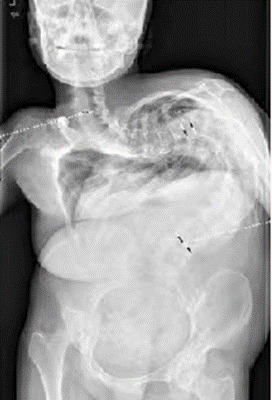

进一步检查发现,小新肺功能已受损50%以上。若不治疗,病情继续加重,可能失去手术机会。但19年日积月累的生长,整个脊柱歪歪扭扭,侧凸、后凸角度都在160度以上,最弯的地方,几乎窝成了直角,像是个大大的“U”,矫形非常困难。

小新脊柱侧后凸畸形重度

小新脊柱侧后凸畸形重度考虑到小新重度脊柱侧后凸畸形,手术难度大、风险高,邱勇教授给出了先牵引、后手术的治疗方案。